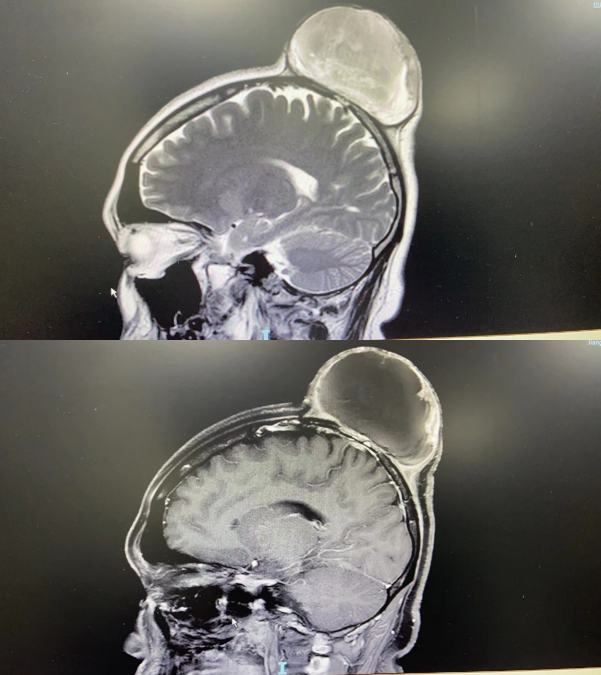

核磁共振提示恶性肿瘤侵犯颅骨

烧伤整形与创面修复外科主治医师余文昊安排患者住院后,立即询问其病史。李小姐说,在3年前曾在外院行头部肿物切除术,当时病理提示“隆突型皮纤维肉瘤”,术后不久就复发了,隆起再次增大,并长得很快。为解决头部的肿瘤病情,这次李小姐选择住院治疗。

烧伤整形与创面修复外科主任曾荣洽立即召集同组医生展开病例讨论,并咨询神经外科副主任医师王康的意见。经过讨论、分析后一致决定,行头部恶性肿瘤切除+部分颅骨切除,钛网修复缺损颅骨,再以吻合血管的游离背阔肌肌皮瓣配合植皮的方式,解决患者肉瘤切除后遗留的创面。术后,患者顺利康复出院。